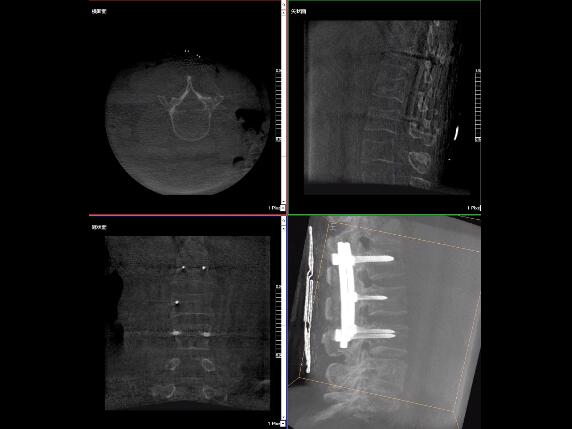

比如,醫(yī)生在做PKP(椎體成形術(shù))的時(shí)候,或者在置入螺釘?shù)臅r(shí)候,醫(yī)生需要在影像上看到螺釘打進(jìn)去的進(jìn)針點(diǎn)以及進(jìn)針的路徑。比如,我們?cè)诖蜓档尼斪訒r(shí)需要看到“貓眼”。我們只有把釘子完全打在“貓眼”里面,才能確保釘子打在了椎弓根里,所以對(duì)“貓眼”的顯影就非常重要。

“貓眼”指的是椎弓根在正位的投影。

最后我要強(qiáng)調(diào)一點(diǎn),以上我提到的“貓眼”,在二維的X光片上,醫(yī)生是靠經(jīng)驗(yàn)去判斷釘子是否打在椎弓根里,這個(gè)時(shí)候如果我們的設(shè)備再先進(jìn)一點(diǎn),診斷手段再多一點(diǎn),如果我們能夠把二維的影像轉(zhuǎn)換為三維的影像,可能就不會(huì)完全依賴醫(yī)生的經(jīng)驗(yàn)。

我們可以在三維的圖像中直觀的看到釘子到底在不在椎弓根里面,這樣可以指導(dǎo)我們準(zhǔn)確的進(jìn)針,指導(dǎo)我們進(jìn)行一場(chǎng)高質(zhì)量的手術(shù),可以起到事半功倍的效果,手術(shù)會(huì)簡(jiǎn)單得多,病人的預(yù)后也會(huì)好得多。